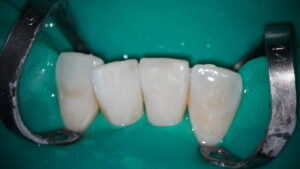

画像がぼやけてしまいましたが、綺麗に修復できました。顕微鏡(マイクロスコープ)を使用して精密なダイレクトボンディングができ、患者様も大変喜んでいただけました。